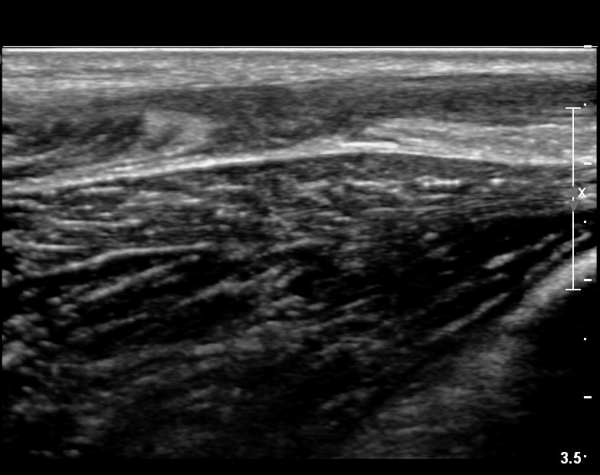

[¹ß¸ñ] simultaneosus tear of GCM and achiles tendon

pain on rt. leg( du: 1 day)

abrupt leg pain developed during foot volleyball

he walk with severe limping with no weight bearing on rt. leg. on examination, there is local tendernes at GCM and achiles tendon, severe pain with ankle dorsiflexion.

ÃÊÀ½ÆÄ °Ë»ç